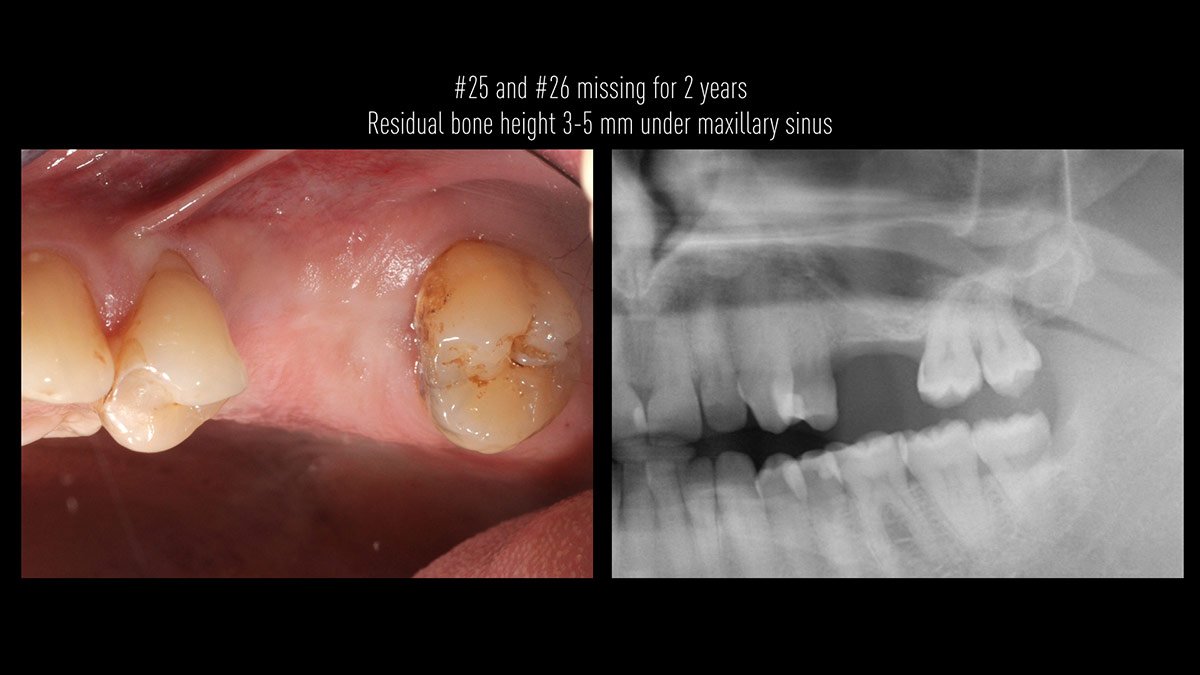

Delayed implant placement; sinus floor elevation by means of lateral approach and implant placement with GBR. Case report by Irfan Abas, M.Sc.